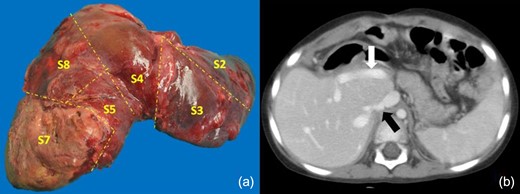

Tumor staging revealed a PRETEXT IV hepatoblastoma (Fig. 1a) with Alpha-fetoprotein (AFP) levels of 1 059,240 ng/ml. After 15 days in the ICU, when the patient’s condition had improved, we initiated NACT (3 courses of Doxorubicin and Carboplatin). At its completion, the AFP levels had decreased to 1 573 ng/ml and a follow-up CT scan showed tumor involvement of segments 1-7 except for s6 (POST-TEXT IV). The latter segment was vascularized through the IRHV but it was deemed insufficient (FLR 21.34%) (Fig. 1b). The absence of a liver donor within reasonable time prompted a multidisciplinary committee meeting that approved an ALPPS procedure after securing informed consent from the parents.

(a) Tumor staging CT (PRETEXT IV), shows all liver sections being invaded by tumor (b) The CT scan post NACT indicates partial tumor response, with persistence of tumor compromising the four sections (POST-TEXT IV). The IRHV is identified (white arrow). No tumor is visible in s6 (c) First stage of ALPPS, the posterior pedicle and its branches were tagged and s7 pedicle clipped (d) FLR on PO15 is outlined in white. The white arrow shows the transection plane.